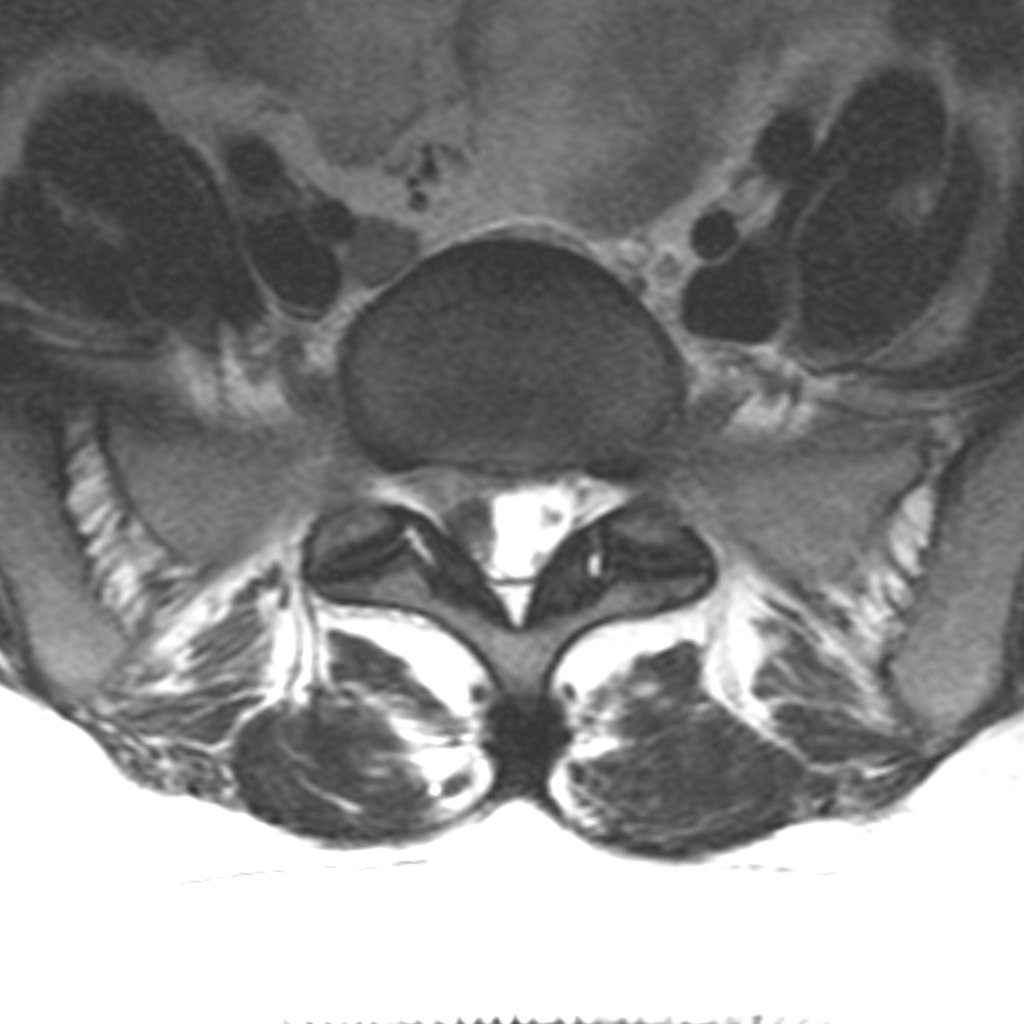

RMN: stare postoperatorie — rădăcina nervoasă este decomprimată

Procedura implică expunerea coloanei printr-o incizie mică (2–3 cm) și crearea unei ferestre osoase minimale între două vertebre. Prin aceasta, hernia care comprimă nervul este îndepărtată și elementele neurale sunt decomprimate.

Nu există diferență clinică semnificativă între metodele disponibile — convențională, microdiscectomie și discectomie endoscopică. Ori de câte ori este posibil, prefer abordarea minim invazivă.